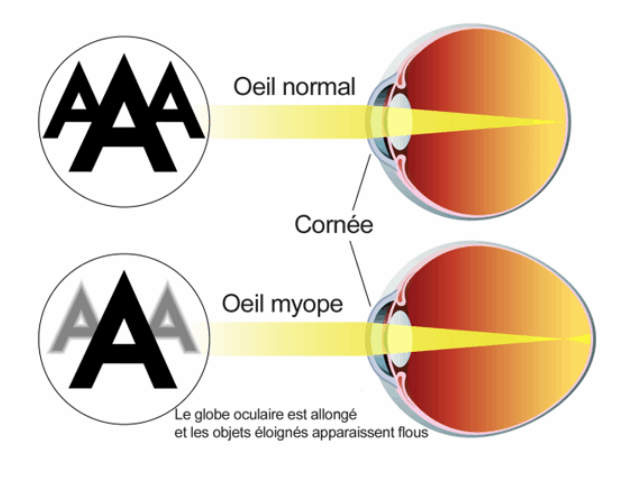

Les principaux défauts de la vision:

- La vision est nette de près et floue de loin dans le cas d'une personne myope. L'oeil est trop long et/ou la cornée trop bombée. Par conséquent l’image se forme en avant de la rétine. Ce défaut apparaît généralement au cours de l’enfance ou de l’adolescence et se stabilise chez l’adulte jeune.